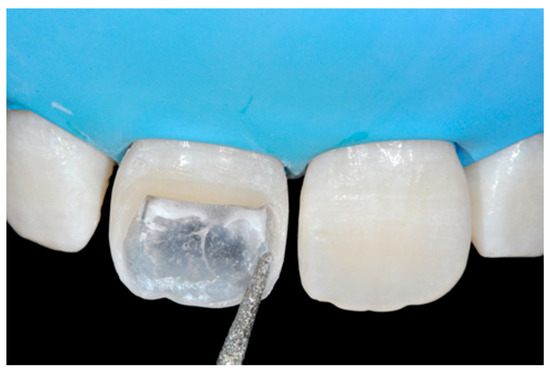

The internal ones can be reduced with diamond burs (WL 268 014 Horico, Berlin, Germany) (Figure 8).

Figure 8.

Excessive thickness of interproximal walls is reduced with a low-speed diamond bur. Reprinted from Restauri diretti nei settori anteriori, G. Paolone, S. Scolavino, © 2021, with permission from Quintessence Publishing Italy.